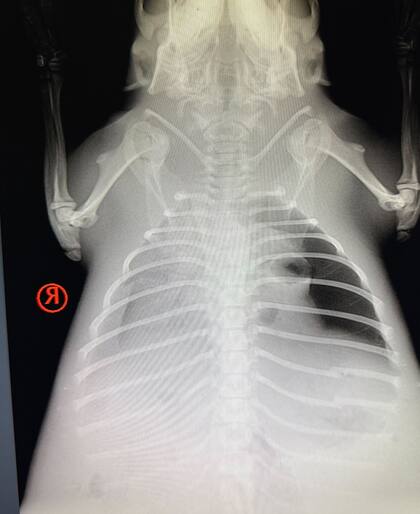

Como parte de la evaluación diagnóstica, se tomó una muestra de sangre de la cola y se le hicieron radiografías. “Las imágenes revelaron un aumento significativo de la opacidad en el campo pulmonar derecho, un hallazgo que podría indicar neumonía o líquido por casi ahogamiento, así como un traumatismo en el lado izquierdo”.